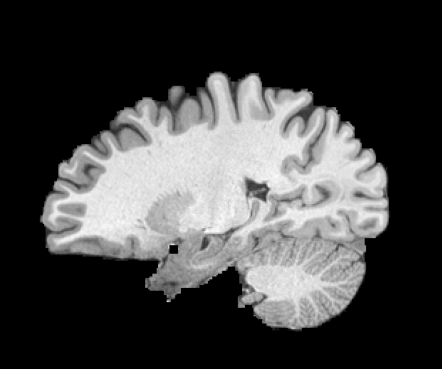

Inverse consistent rigid, affine, nonparametric, and MLP registration. We train networks on MNIST 5s using the methods in Secs. 3 and 4, demonstrating that the resulting networks are inverse-consistent. Our TwoStepConsistent (TSC) operator can be used on any combination of the networks defined in Sec. 3. For demonstrations, we join an MLP registration network to a vector field registration network, and join two affine networks to two vector field networks. Fig. 2 shows successful inverse-consistent sample registrations.

HCP Brain MRI We train on 1076 brain-extracted T1w images from the HCP dataset [24] and test on a sample of 100 pairs between 36 images via mean Dice over 28 midbrain structures [20, 21]. We train and execute the network at [130155130], then compute the Dice score at full resolution.

OASIS Brain MRI We use the OASIS-1 [12] data preprocessed by [9]. This dataset contains images of 414 subjects. Following the data split in [14], we train on 255 images and test on 153 images555Due to changes in the OASIS-1 data, our test set slightly differs from [14]. We evaluate all methods using our testing protocol so that results are consistent.The images in the dataset are of size [160192224], and we crop the center of the image according to the preprocessing in [14], leading to a size of [160144192]. During training, we sample image pairs randomly from the train set. For evaluation, we randomly pick 5 cases as the fixed images and register all the remaining 148 cases to the 5 cases, resulting in 740 image pairs overall.

| Moving Image | Warped Image | Fixed Image | Moving Image | Warped Image | Fixed Image |